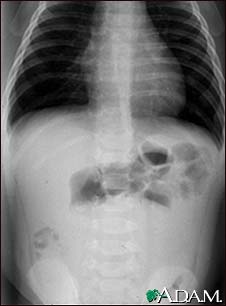

Intussusception - X-ray

This abdominal x-ray shows an intestinal condition in which a loop of bowel has slipped into another section of bowel (intussusception), causing swelling, reduced blood flow, obstruction, and tissue damage. Intussusception requires emergency treatment (barium enema or surgery) to prevent intestinal tissue death (necrosis), intestinal perforation, peritonitis, and death.